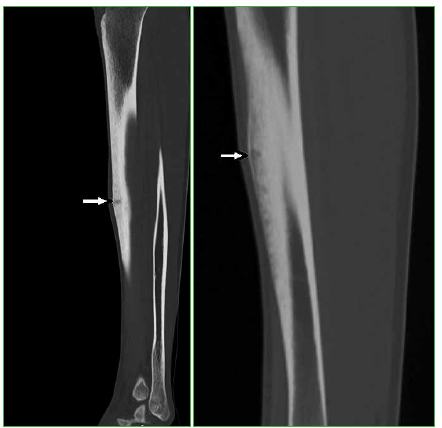

Figura 10.

Osteoma osteoide. Tomografía computarizada, cortes sagitales de la pierna que muestran lesiones hipodensas subcorticales (flechas) que comprometen el periostio de las tibias. Dos atletas presentaron estas lesiones en la tibia.